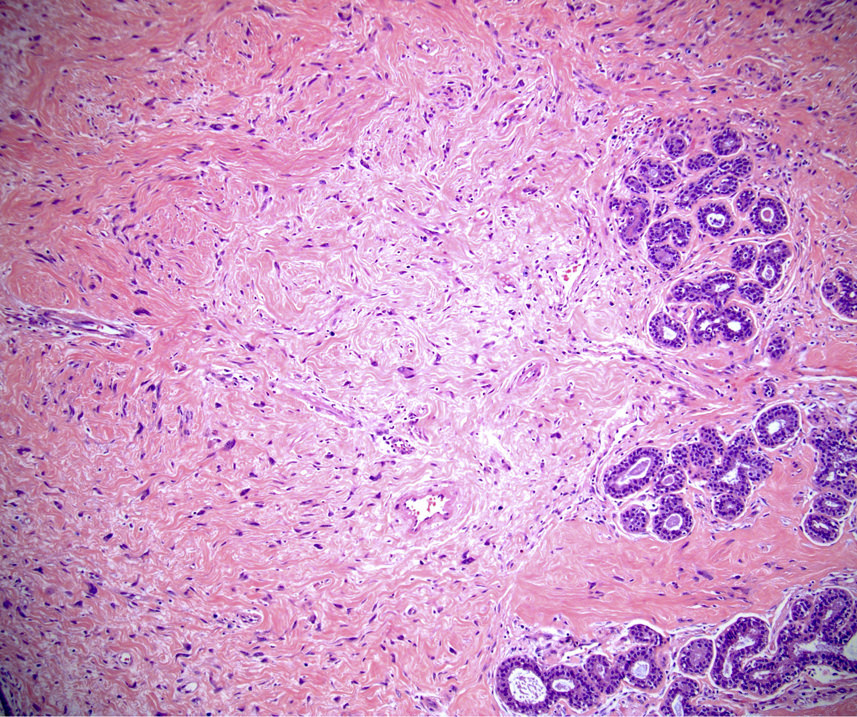

Microscopic (histologic) description

- Well circumscribed, unencapsulated

- Biphasic tumor, proliferation of both glandular and stromal elements

- Glandular component

- 2 recognized growth patterns (of no clinical significance, both patterns may occur within a single lesion)

- Intracanalicular: glands are compressed into linear branching structures by proliferating stroma

- Pericanalicular: glands retain open lumens but are separated by expanded stroma

- Glandular elements have intact myoepithelial cell layer

- Stromal component

- Generally uniform cellularity within a given lesion

- Collagen and bland spindle shaped stromal cells with ovoid or elongated nuclei

- Usually no mitotic activity; rare mitotic activity may be present in young or pregnant patients (Breast J 2017;23:182)

- No stromal atypia

- Stroma may show myxoid change or hyalinization

Microscopic (histologic) images

Contributed by Gary Tozbikian, M.D., Debra Zynger, M.D., Azadeh Khayyat, M.D. and Julie M. Jorns, M.D. (Case #533)